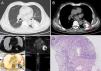

A 67-year-old male presented with a 2-year history of cough and sputum. Three years ago, the patient underwent surgery for a malignant peripheral nerve sheath tumor (MPNST) located on the sole of the foot. Cytokeratin 19 fragment was elevated at 5.6ng/ml. Chest CT revealed an irregular mass in the lower lobe of the left lung with extensive central calcification (Fig. 1A and B). PET-CT showed the mass had high glucose metabolism with an SUVmax of 5.8 (Fig. 1C). And the CT-guided biopsy indicated MPNST with calcification (Fig. 1D). The final diagnosis was MPNST with pulmonary metastasis and calcification. The patient was referred to a specialized hospital for further comprehensive treatment. MPNST is a rare soft tissue sarcoma originating from peripheral nerve sheath cells, with an annual incidence of about 0.001%. It predominantly occurs in adults aged 20–50 years, with the most common primary sites being the limbs (approximately 40%) [1]. Extensive calcification in pulmonary metastasis of MPNST is extremely rare, and the formation of large calcific foci suggests a prolonged and slow disease process, which contradicts the conventional understanding of malignant tumors progressing rapidly.

(A, B) Chest CT: An irregular mass is seen in the lower lobe of the left lung, measuring 57mm×54mm, with central patchy calcification (red arrow). (C) Axial PET-CT fusion image: A hypermetabolic mass in the lower lobe of the left lung with an SUVmax of 5.8. The high metabolic area corresponds to the soft tissue component (red arrow), while the calcified area shows no metabolism (black arrow). (D) Pathological result: Malignant peripheral nerve sheath tumor with calcification.